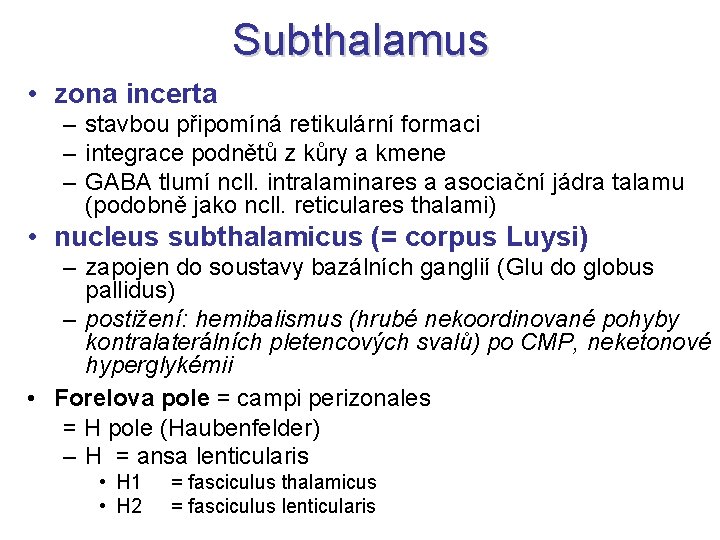

Subthalamus • zona incerta – stavbou připomíná retikulární formaci – integrace podnětů z kůry a kmene – GABA tlumí ncll. intralaminares a asociační jádra talamu (podobně jako ncll. reticulares thalami) • nucleus subthalamicus (= corpus Luysi) – zapojen do soustavy bazálních ganglií (Glu do globus pallidus) – postižení: hemibalismus (hrubé nekoordinované pohyby kontralaterálních pletencových svalů) po CMP, neketonové hyperglykémii • Forelova pole = campi perizonales = H pole (Haubenfelder) – H = ansa lenticularis • H 1 • H 2 = fasciculus thalamicus = fasciculus lenticularis